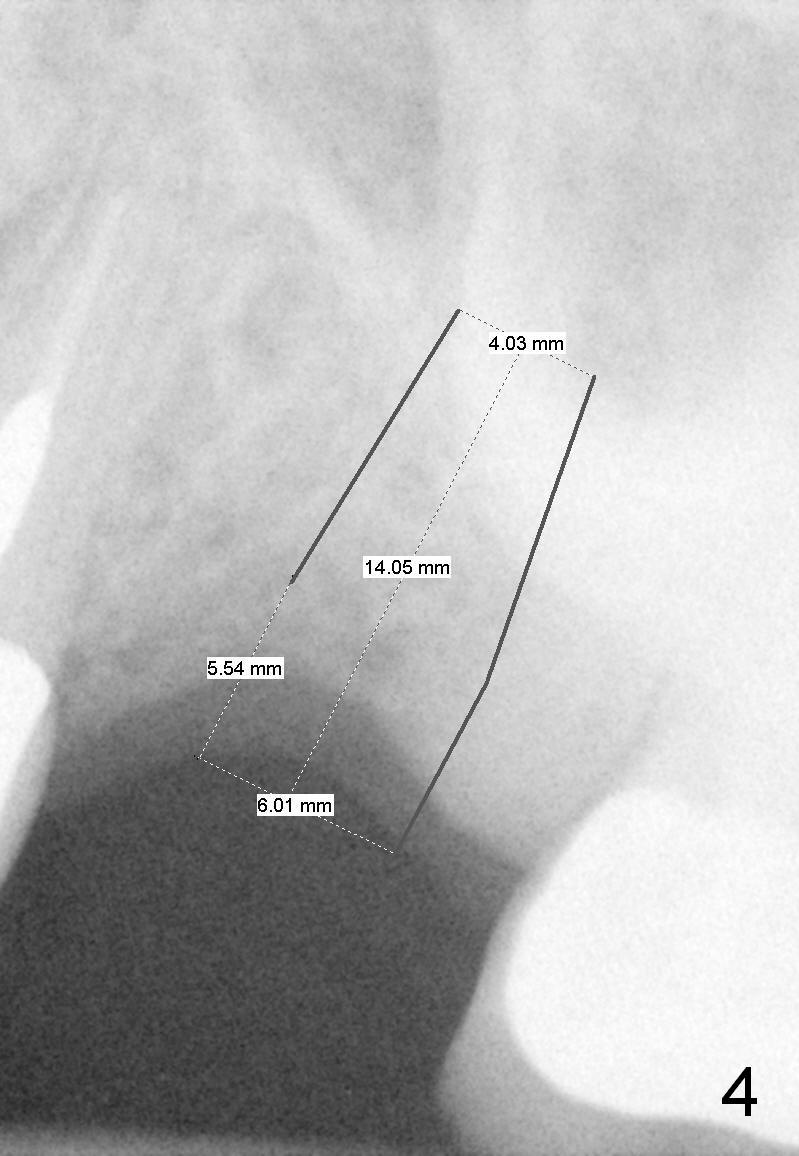

A 58-year-old white woman is afraid of dentistry (Fig1). Two years post extraction of the tooth #14, the bone height reduces by 4 mm (compare Fig.2,3).